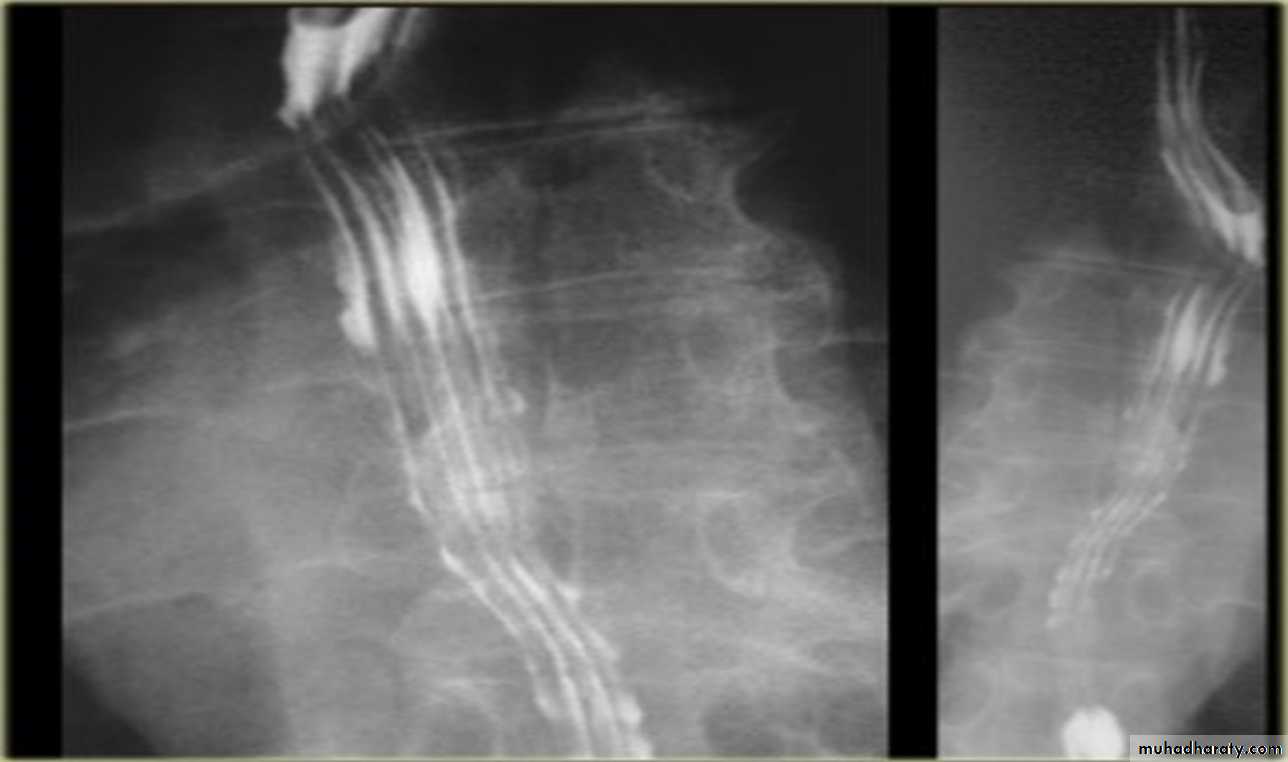

Inflammation and Infection

Gastroesophageal reflux (GERD) is the most common cause of esophagitis.Infectious esophagitis

Candida esophagitis:in patient with an infectious esophagitis due to candida , the barium shows numerous fine erosions & plaques causing shaggy outline of the osophagus due to Candida albicans in immunocompromised patient.

middle year old female with a past medical history significant for HIV/AIDS comes in with complaint of loosing their weight over the past 2 weeks with pain & difficulty on swallowing …. Also feels like food is getting stuck in her throat

What is your diagnosis ??????????